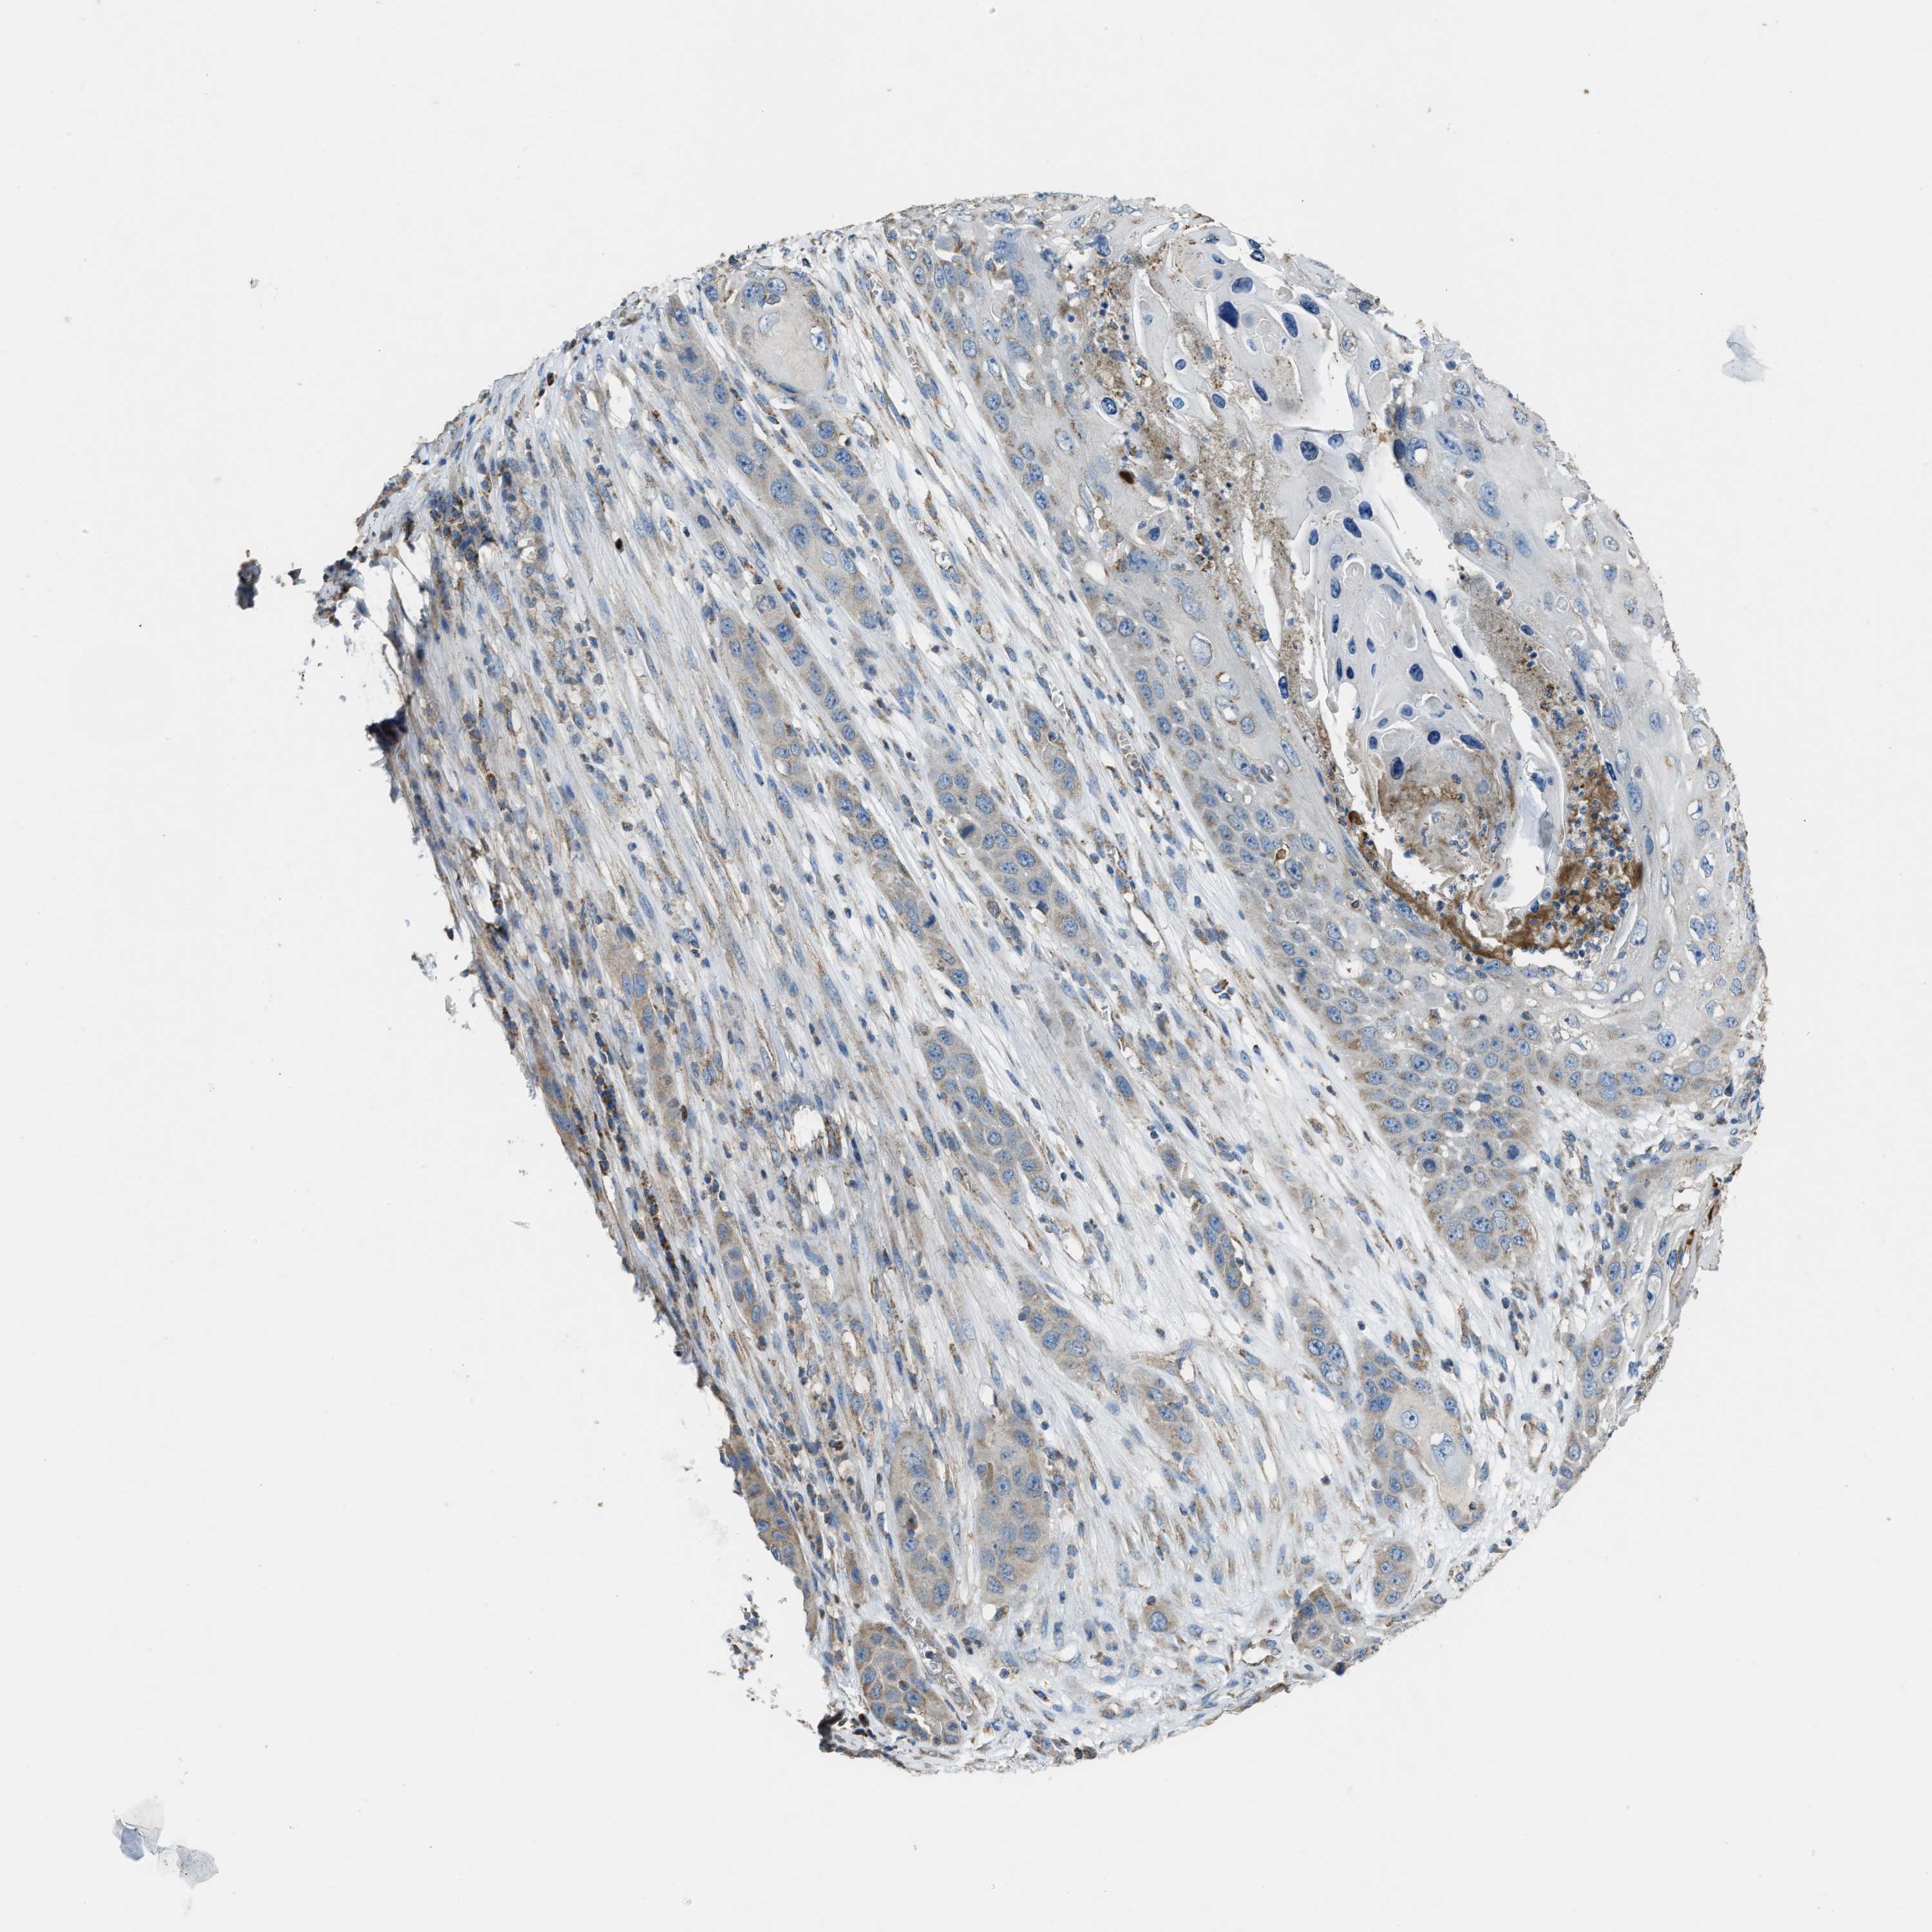

Basal cell and squamous cell cancer

SKIN CANCER - Protein expressioni

A mouse-over function shows sample information and annotation data. Click on an image to view it in a full screen mode. Samples can be filtered based on level of antibody staining by selecting one or several of the following categories: high, medium, low and not detected. The assay and annotation is described here.

Antibody stainingi

Antibody staining in the annotated cell types in the current human tissue is reported as not detected, low, medium, or high, based on conventional immunohistochemistry profiling in selected tissues. This score is based on the combination of the staining intensity and fraction of stained cells.

Each image is clickable and will lead to virtual microscopy that enables deeper exploration of all samples and also displays staining intensity scores, fraction scores and subcellular localization as well as patient and tissue information for each sample.

Antibody HPA021167

Staining

High

Medium

Low

Not detected

Intensity

Strong

Moderate

Weak

Negative

Quantity

>75%

75%-25%

<25%

None

Location

Nuclear

Cytoplasmic/membranous

Cytoplasmic/membranous,nuclear

Squamous cell carcinoma, metastatic, NOS

Squamous cell carcinoma, NOS